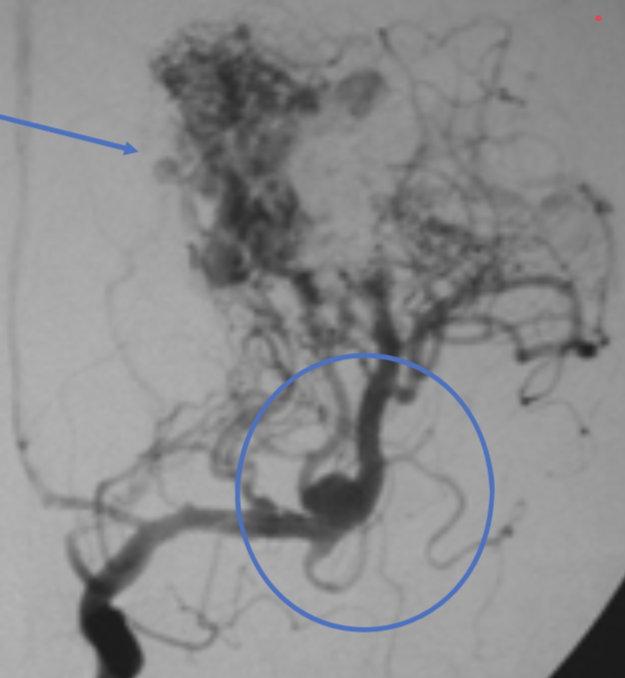

AVM - architecture

AVM - nidus:

AVM - topography and vessels involved